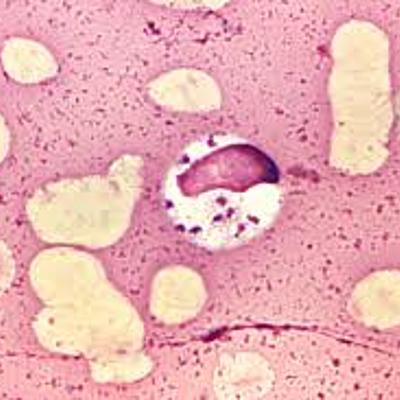

Ciclos vida de protozoos y nematodos sanguíneos